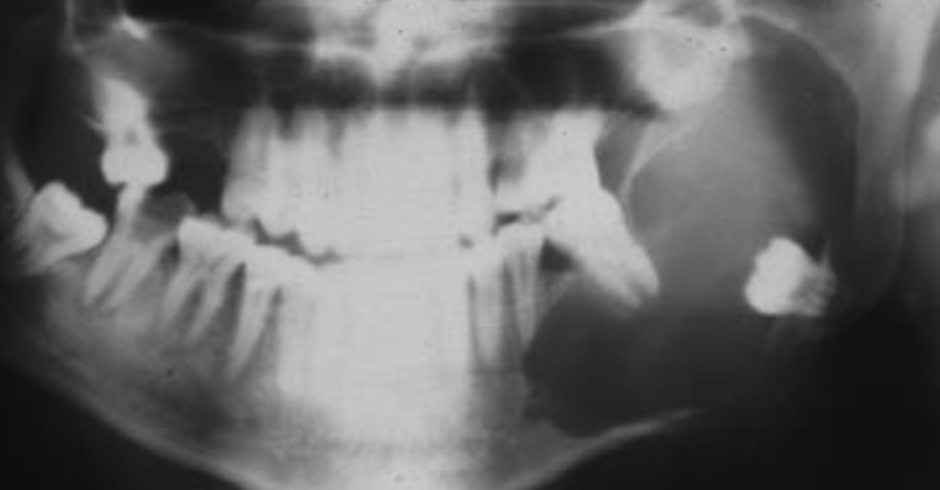

Q

A

Dentigerous cyst

8

Dentigerous cyst (expansion of)